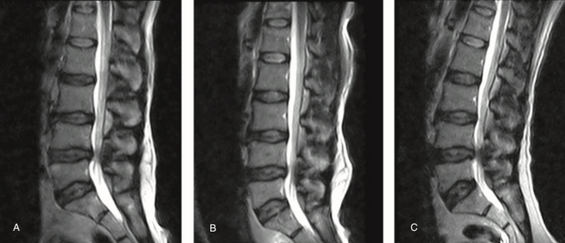

腰椎MRI阅片,一定要注意这些细节!